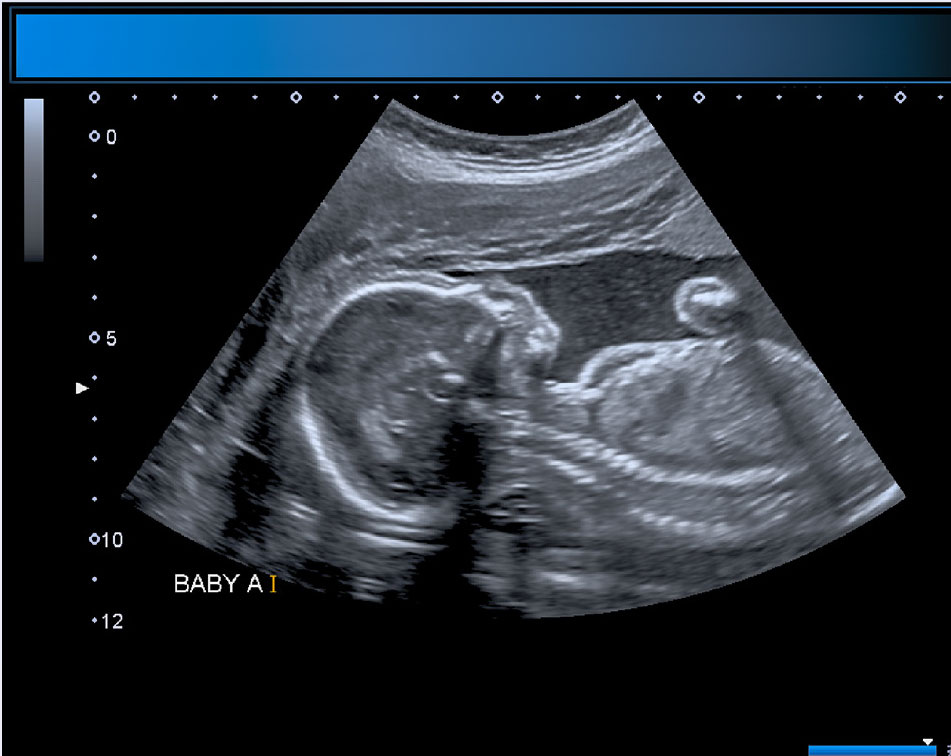

- LCCC offers 3-D/4-D technology and will attempt to obtain beautiful images for keepsakes. The quality of the images obtained will depend on the baby's position and cooperation.

- LCCC students will provide volunteers with printed paper images from the session.

- LCCC students will provide volunteers with a USB with images from the session.